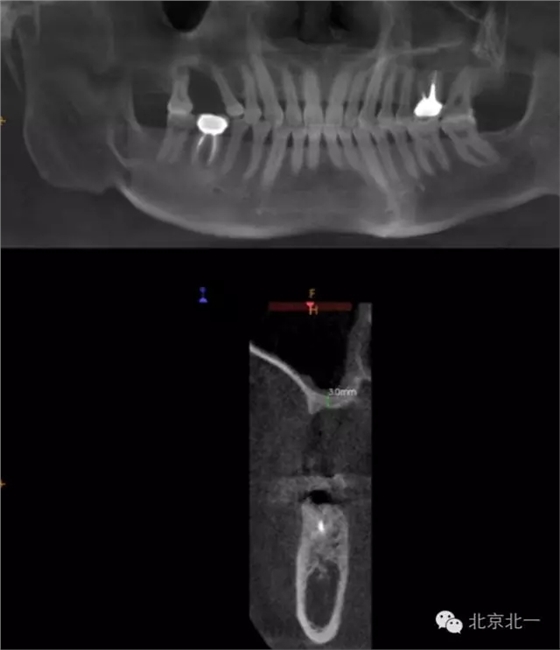

CBCT顯示,骨寬度可,骨高度不足,月3mm。頜間距離增大。

圖二:手術前全景片

圖三:骨高度3mm.

圖十八:手術前CBCT